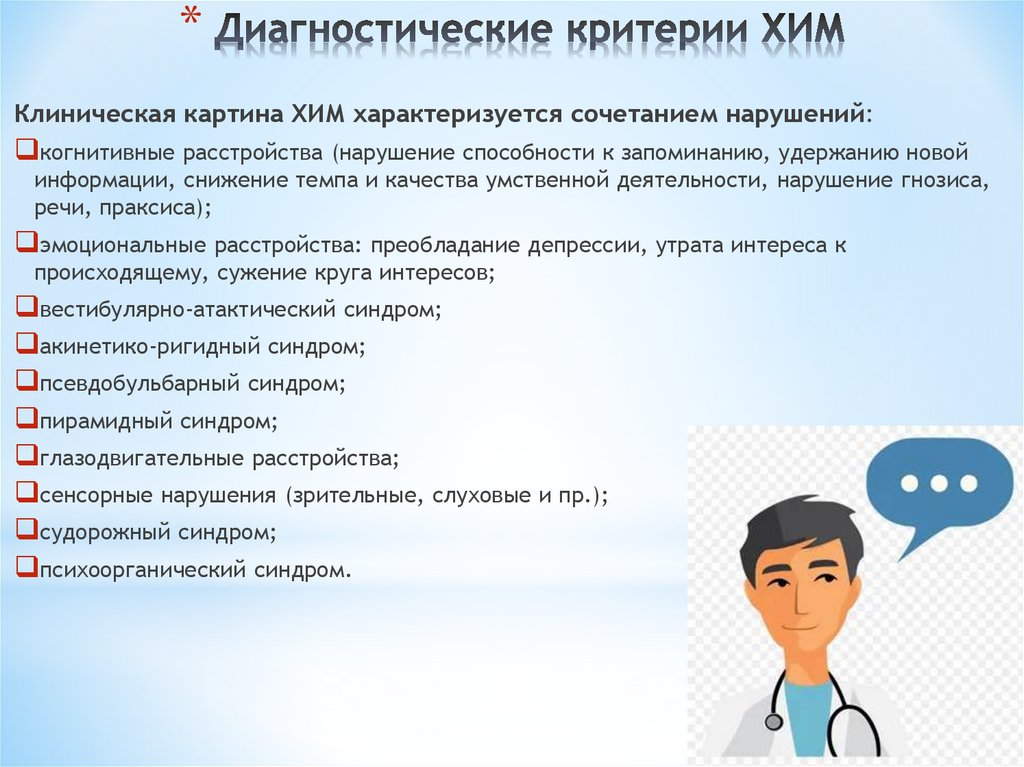

Хроническая ишемия головного мозга и лейкоареоз: симптомы и лечение